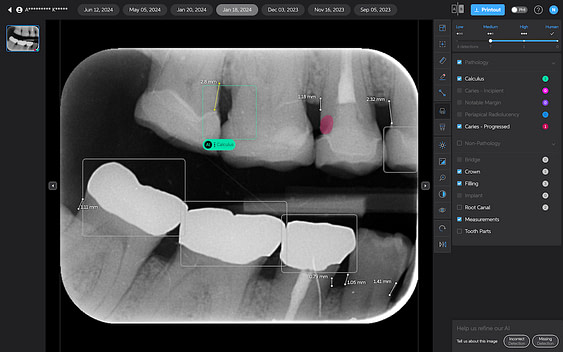

Caries Detection

The best for last and arguably the most well-thought-out feature. Especially with the tooth segmentation mode, which makes it easier for patients to understand their diagnosis and treatment plans.

The system uses two shades of pink to indicate potential caries:

- Light pink: Incipient caries (100% in enamel) - we will often review

- Darker magenta: Caries extending into dentin - we need to restore

The system even provides a percentage breakdown of enamel vs. dentin involvement. I have been blown away by its accuracy while using it, and it makes something that feels quite subjective (reading shades of grey) into a science.

This feature is very useful for patient education and deciding between preventive measures and restorative treatment. However, remember that radiographic evidence alone is not always sufficient for a definitive caries diagnosis.

Sometimes AI doesn’t get it right.

AI is just a tool, and those who think it will get it right and 100% correct each time are thinking of this in the wrong way.

I view Pearl and Second Opinion as a method to standardize diagnosis, educate, and, most importantly, to function as a patient communication tool.

Sometimes, AI does not get it right and does not pick up anything. Or sometimes the detection is wrong, and you should only use it to focus your attention on potentially crucial areas but still make a call yourself.